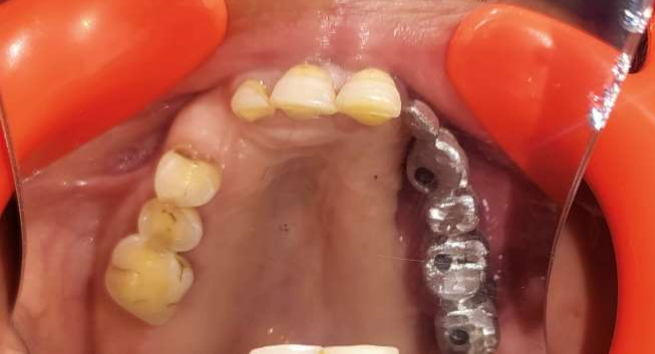

A 55-year-old man was referred to the Department of Prosthodontics with complaints of hypernasal speech, nasal regurgitation, and oroantral communication. He had undergone post Mucormycosis partial maxillectomy (Left Maxilla) and had not received any prosthetic rehabilitation (Figure 1). The patient presented with oroantral communication and difficulty in speech and mastication.

Figure 1: Maxillary defect post Mucormycosis

Figure 1